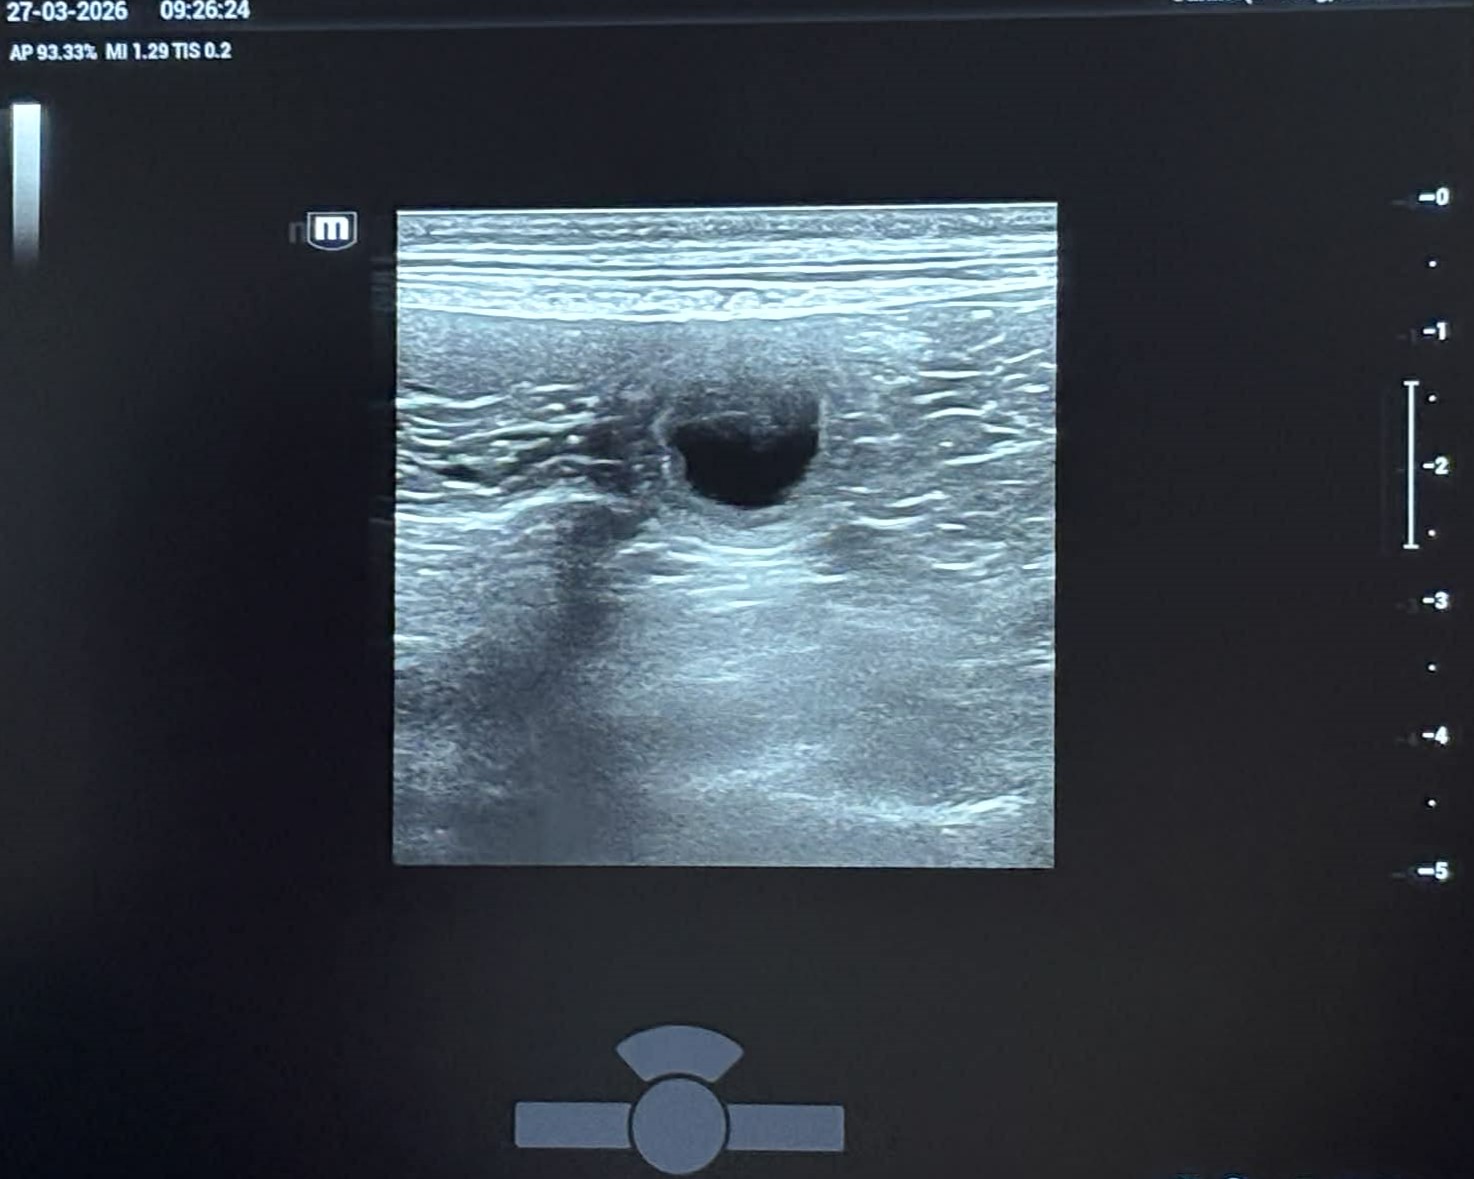

Opdatering: Uge 13

Lola er blevet scannet, og hun er med hvalpe. Hendes apetit er øget og hendes mave er voksende. Hun er blevet meget mere kærlig og kælen.

Vi ser frem til at hilse på de små hvalpe, når de fødes i uge 19.